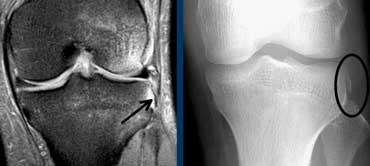

Trên X-quang, một dấu hiệu gián tiếp quan trọng của đứt ACL là gãy xương Segond.

Khó nhận thấy trên MRI nhưng dễ phát hiện hơn nhiều trên phim X-quang thường.

Gãy xương Segond là gãy xương bong điểm bám của dải bên ngoài do cơ chế xoay trong và lực vẹo trong.

Trong 75-100% trường hợp sẽ kèm theo đứt ACL.

Bong gân bánh chè dạng vỏ bọc (Patellar sleeve avulsion). Đường gãy chỉ nhìn thấy trên ảnh mặt phẳng đứng ngang (coronal).

Bong gân bánh chè dạng vỏ bọc (Patellar sleeve avulsion).

Ở trẻ em, tình huống có sự khác biệt. Trẻ em không phát triển bệnh lý gân.

Trường hợp bên trái là hình ảnh của một bé gái bị đau dưới xương bánh chè sau khi tập thể dục dụng cụ.

Mặc dù X-quang bình thường, thực tế có một đường gãy qua phần sụn của cực dưới xương bánh chè.

Trên MRI, hình ảnh trông giống như Jumper’s Knee ở trên. Chỉ trên ảnh mặt phẳng đứng ngang mới thấy được đường gãy giảm tín hiệu nằm trong phần sụn tăng tín hiệu.

Thông thường các gãy xương này được điều trị bằng khâu phục hồi.

Khi các tổn thương này không được phát hiện, chúng sẽ lành với sự hình thành cốt hóa ngay dưới xương bánh chè.